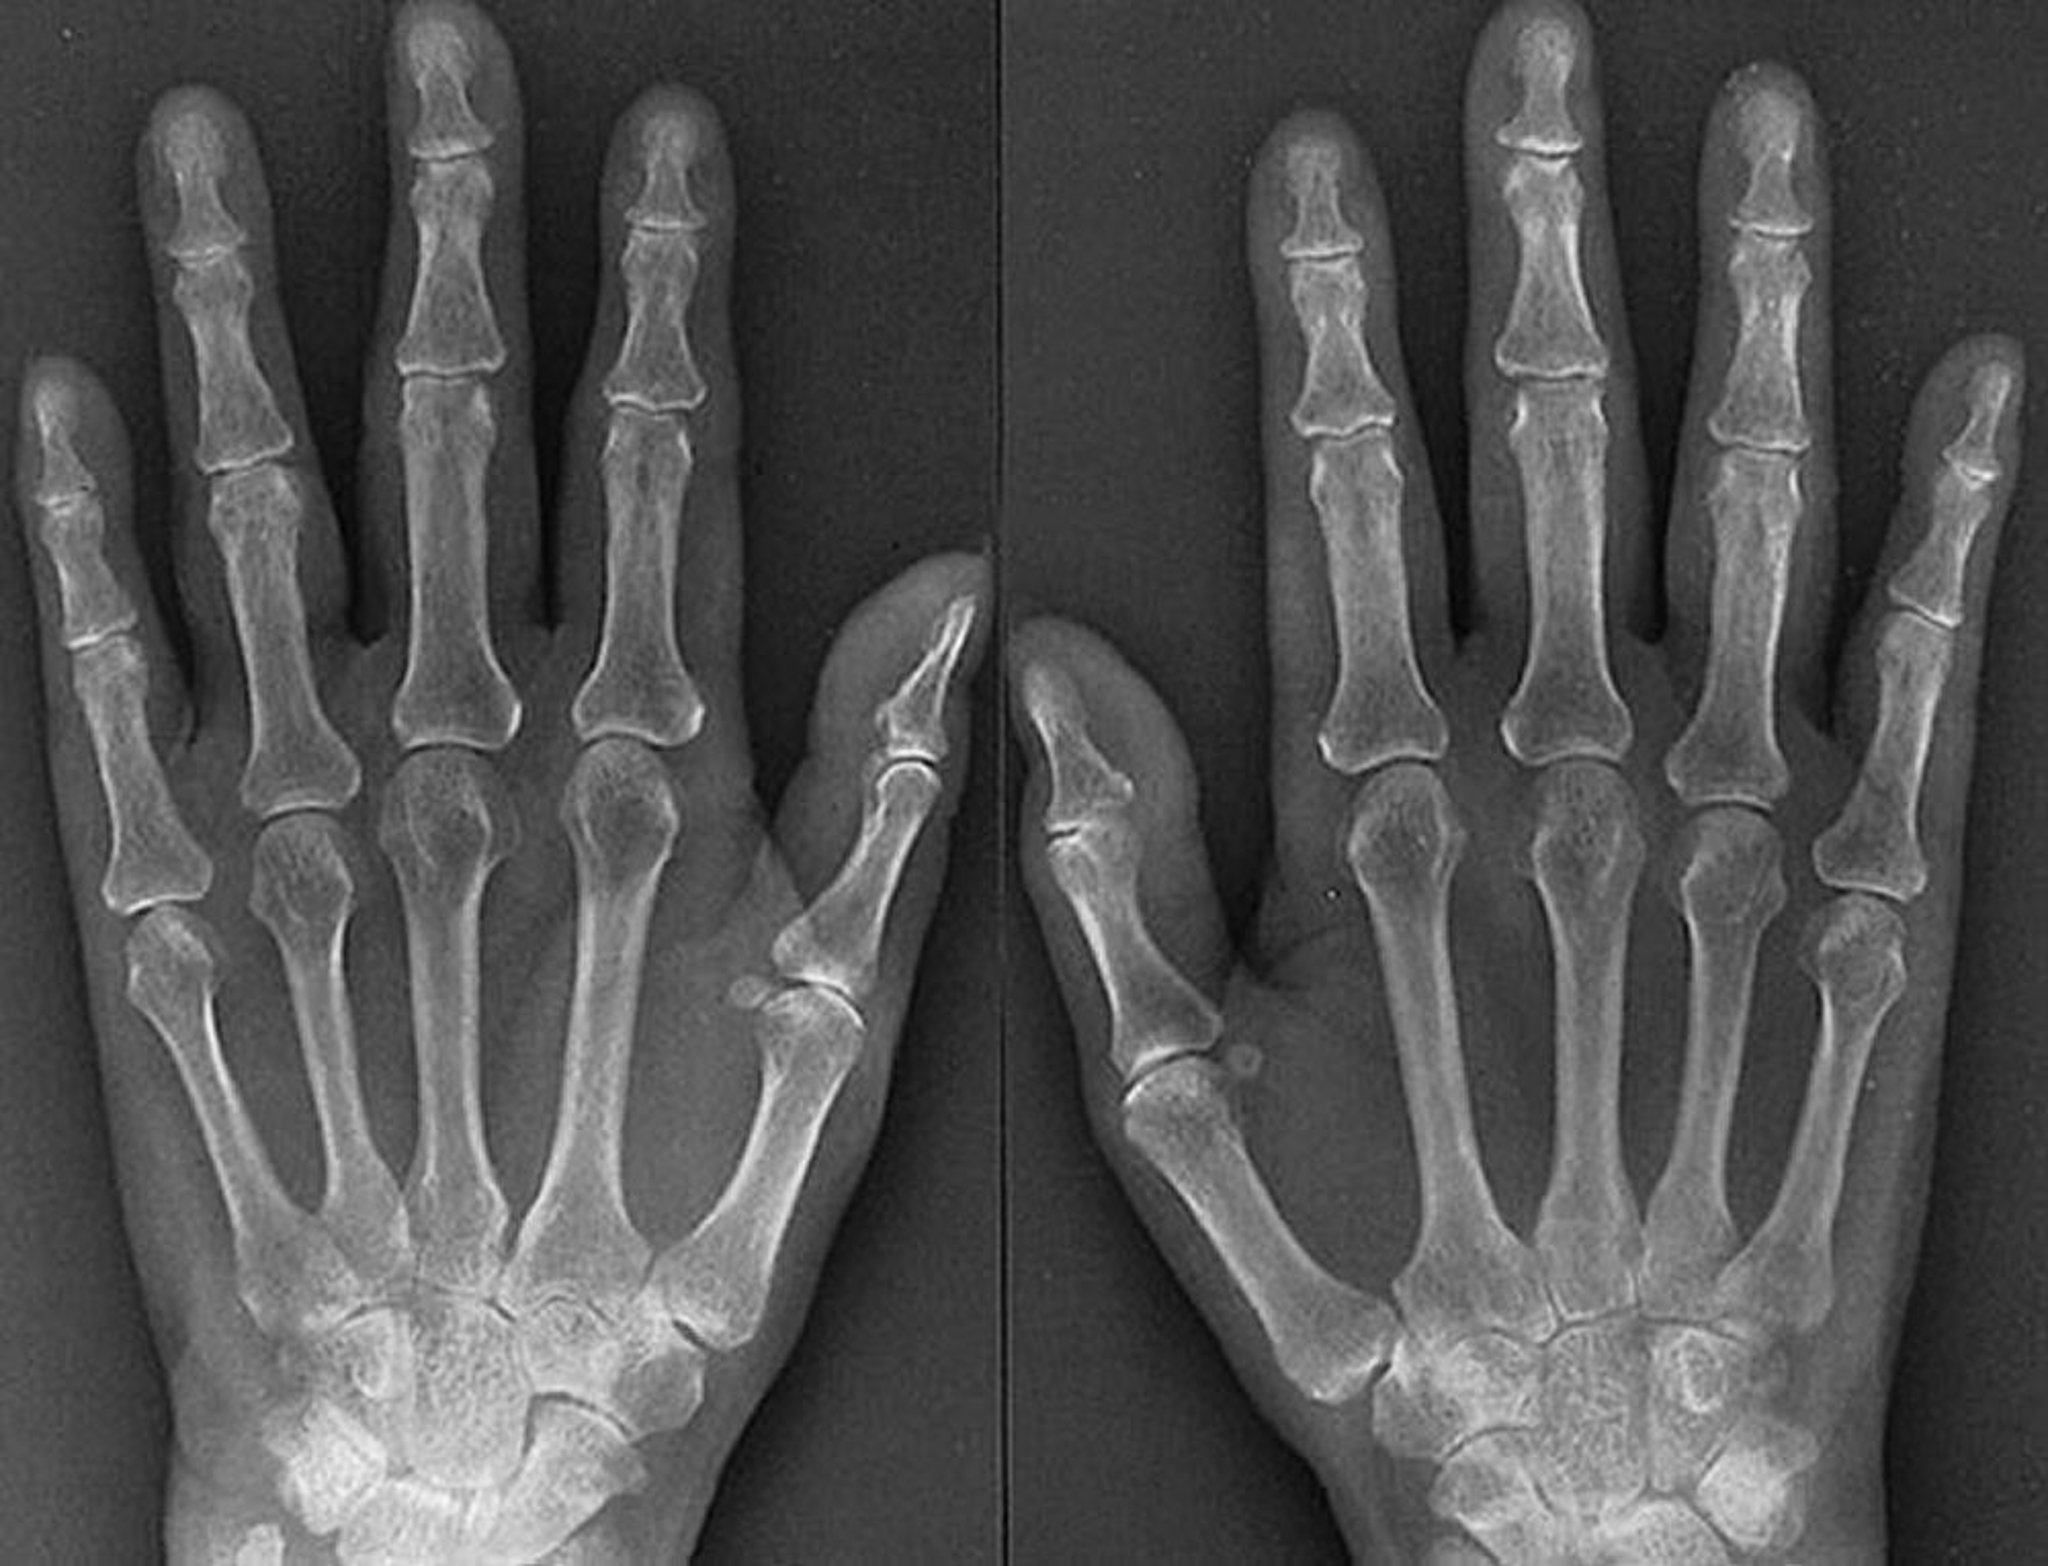

Caractéristiques radiographiques de la polyarthrite rhumatoïde précoce

Les caractéristiques d'une polyarthrite rhumatoïde agressive et précoce, comme on les voit sur cette radiographie d'une femme de 61 ans qui a eu une polyarthrite rhumatoïde pendant 1 an, comprennent des signes de gonflement des tissus mous des articulations métacarpophalangiennes et interphalangiennes proximales, une ostéoporose périarticulaire, un rétrécissement symétrique de l'espace articulaire de plusieurs articulations métacarpophalangiennes et interphalangiennes proximales des deux mains et des érosions subtiles des 3e et des 4e articulations métacarpophalangiennes droites et gauches.

By permission of the publisher. From Matteson E, Mason T: Atlas of Rheumatology. Edited by G Hunder. Philadelphia, Current Medicine, 2005.